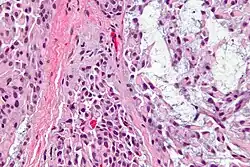

Миоэпителиа́льные кле́тки (иногда называемые миоэпите́лием) представляют собой клетки, обычно обнаруживаемые в железистом эпителии в виде тонкого слоя над базальной мембраной, но обычно под просве́тными клетками. Они могут быть положительными для альфа-актина гладких мышц и могут сокращаться и выделять секреты экзокринных желез. Они обнаружены в потовых, молочных, слезных и слюнных железах. Миоэпителиальные клетки в этих случаях составляют базальный клеточный слой эпителия, который содержит эпителиальный предшественник. В случае заживления ран миоэпителиальные клетки реактивно пролиферируют. Наличие миоэпителиальных клеток в гиперплазированной ткани свидетельствует о доброкачественности железы, а отсутствие указывает на рак. Только редкие виды рака, такие как аденоидно-кистозные карциномы, содержат миоэпителиальные клетки в качестве одного из злокачественных компонентов.

Миоэпителиальные клетки являются настоящими эпителиальными клетками, положительными для кератина, не путать с миофибробластами, которые являются настоящими мезенхимальными клетками, положительными для виментина. Эти клетки, как правило, положительны в отношении альфа-актина гладких мышц (αSMA), цитокератина 5/6 и других высокомолекулярных цитокератинов, p63 и кальдесмона. Миоэпителиальные клетки имеют звездчатую форму и также известны как корзинчатые клетки. Они лежат между базальной мембраной и железистым эпителием. Каждая клетка состоит из клеточного тела, от которого расходятся 4-8 отростков, охватывающих секреторную единицу. Миоэпителиальные клетки обладают сократительной функцией. Они способствуют выведению секрета из просвета секреторных единиц и облегчают движение слюны по слюнным протокам.